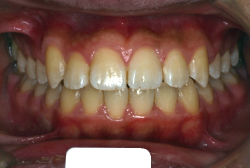

「歯並びの凸凹を直したい」という主訴で来院したケースです。診断の結果、たしかに「叢生」という隙間が足りないと言うことが原因の凸凹症例でした。

しかし、それ以上に問題なのは「前歯の噛み合い方が深すぎる」という症状で、初診の歯の正面写真を見ると下の前歯が全く見えません。こういう症状を矯正学では「過蓋咬合(かがいこうごう)」と言います。過蓋咬合を放置すると、将来的に顎関節に悪影響を与えるとされており、顎関節症の原因因子の一つです。また下の前歯の先端が、上の前歯の裏側の歯茎と強く接触するため、歯周病の原因にもなります。

検査の結果、凸凹が軽症なため非抜歯で矯正すること可能と判断、マルチブラケット装置にて治療しました。治療後は歯並びが綺麗になっただけでなく、噛み合わせ的にも正しい状態が確立しています。